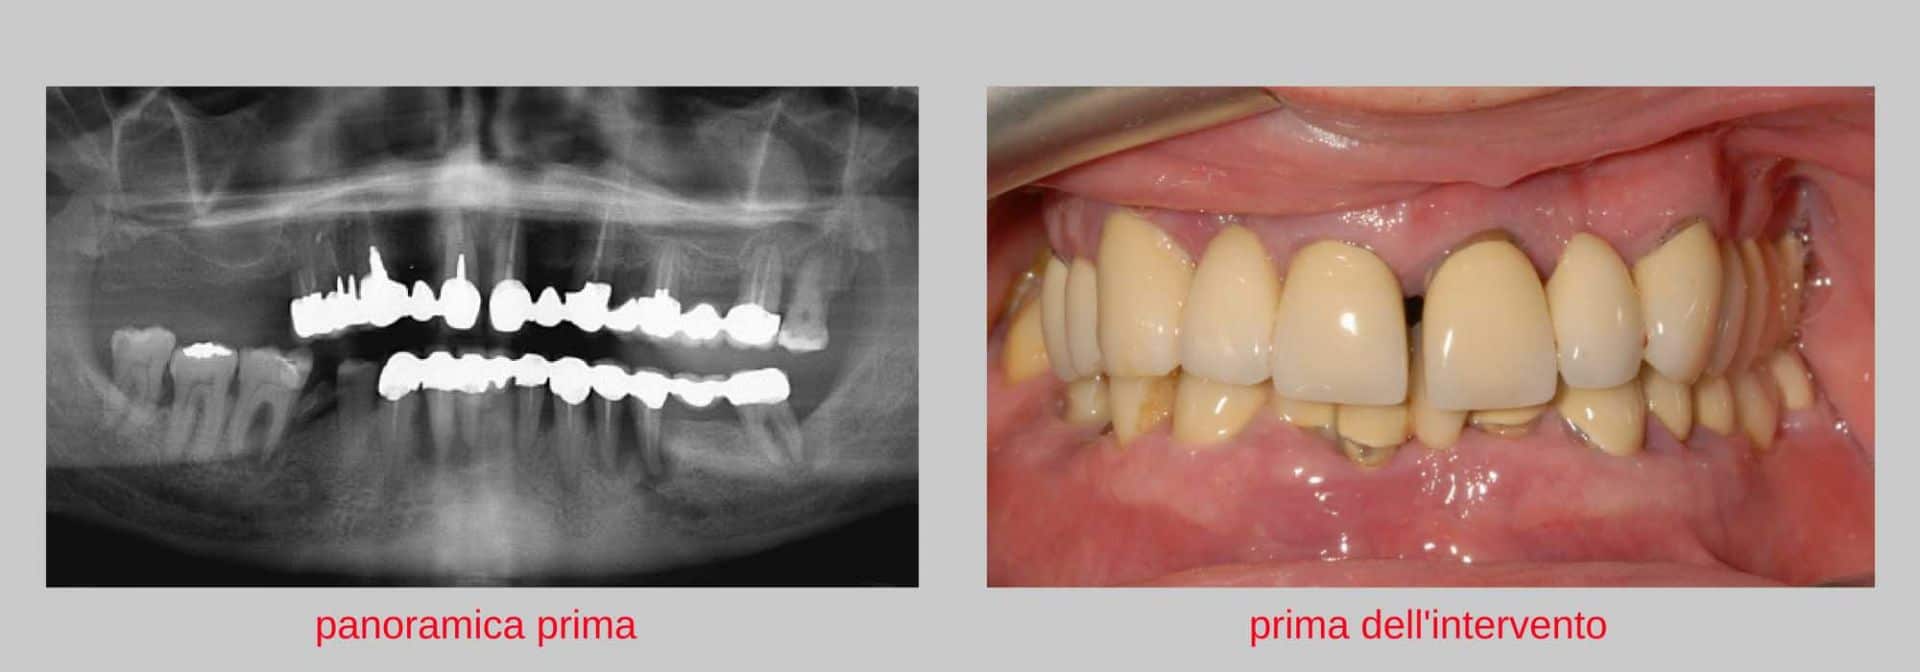

E’ stata effettuata al paziente una panoramica ed una TAC Cone Beam. La quantità di osso sia nell’arcata superiore, che nell’arcata inferiore era estremamente limitata a causa di numerose infezioni che avevano distrutto parte dell’osso.La situazione era particolarmente grave nella zona premolare e molare destra dell’arcata inferiore. I denti dell’arcata superiore e dell’arcata inferiore erano gravemente compromessi a causa di lesioni parodontali, cariose ed endodontiche (granulomi). Erano tutti denti, in sostanza, irrecuperabili.